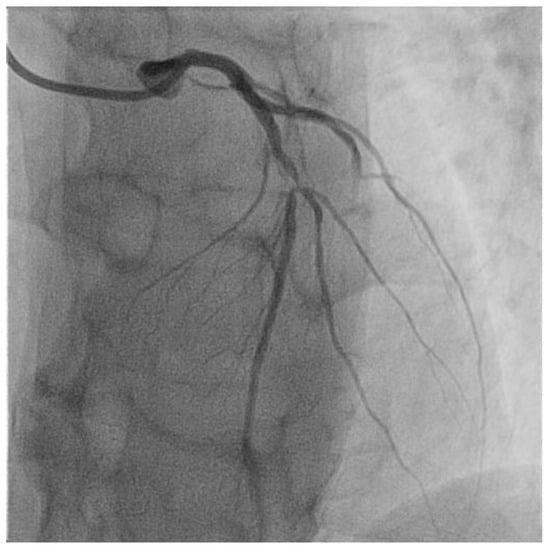

Figure 2.

Selective angiography of the left coronary artery. Severe focal atherosclerotic narrowing of the proximal segment of left anterior descending coronary artery.